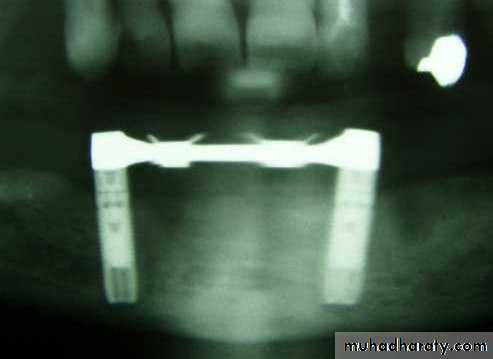

These implants are primarily used in patients with severely resorbed ridges. The implant is inserted through the inferior border of the mandible and into the edentulous area.Copyright © 2009, 2006 by Saunders, an imprint of Elsevier Inc. All rights reserved.

In any case, these implants are used in mandibles only and are secured at the lower border of the chin via bone plates. These were originally designed to have a secure implant system, even for very resorbed lower jaws.

A typical Transosseous Implant. The plate on the bottom is firmly pressed against the bottom part of the chin bone, whereas the long screw posts go through the chin bone, all the way to the top of the jaw ridge inside the mouth. The two attachments that will eventually protrude through the gums can be used to attach an overdenture-type prosthesis.

The plate

long screw postsThe two attachments